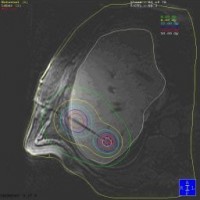

This is followed by the computer-assisted calculation of a radiation plan and computer-controlled insertion of the radiation source into the tumor via the catheters.

Images: Brachytherapy for liver metastases: first MRI-guided placement of one catheter per tumor followed by irradiation through the catheters using Iridium 192 radiation source.